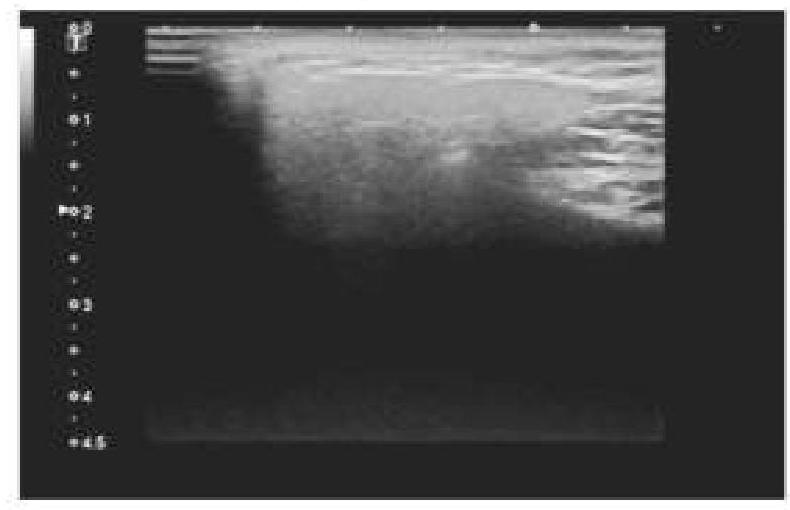

A 45-year-old patient complained of pain on one side of the neck. She is afraid of eating food as it worsens the pain. An ultrasound of the salivary glands is shown below. What is the most likely diagnosis?

Explanation: ***Sialolithiasis*** - The ultrasound image shows an **echogenic focus** with clear **posterior acoustic shadowing** within the salivary gland, which is characteristic of a salivary gland stone. - The patient's symptoms of **pain on one side of the neck** and **worsening pain with eating** (likely due to salivary stimulation) are classic for **sialolithiasis**, as the stone obstructs salivary flow. *Salivary gland foreign body* - While a foreign body could present with similar pain, it would typically appear as a distinct object on ultrasound, but its echogenicity and shading characteristics might differ depending on the material. - The history of a foreign body ingestion or insertion would be crucial, which is not mentioned here. *Cervical lymphadenopathy* - **Lymph nodes** on ultrasound typically appear as oval-shaped structures with a **hypoechoic cortex** and an **echogenic hilum**; they do not usually show significant acoustic shadowing unless calcified. - While cervical lymphadenopathy can cause neck pain, it is not typically exacerbated by eating in the same way an obstructed salivary gland would be. *Osteoma of the floor of the mouth* - An **osteoma** is a **benign bone tumor** that would present as a very **dense, highly echogenic mass** with severe posterior acoustic shadowing on ultrasound, originating from bony structures. - While an osteoma could cause pain, its location (floor of the mouth) and nature would not typically explain pain worsening specifically with eating due to salivary gland obstruction.